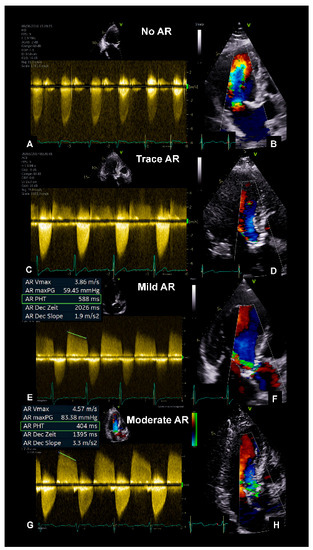

2.3. Aortic Valve Regurgitation